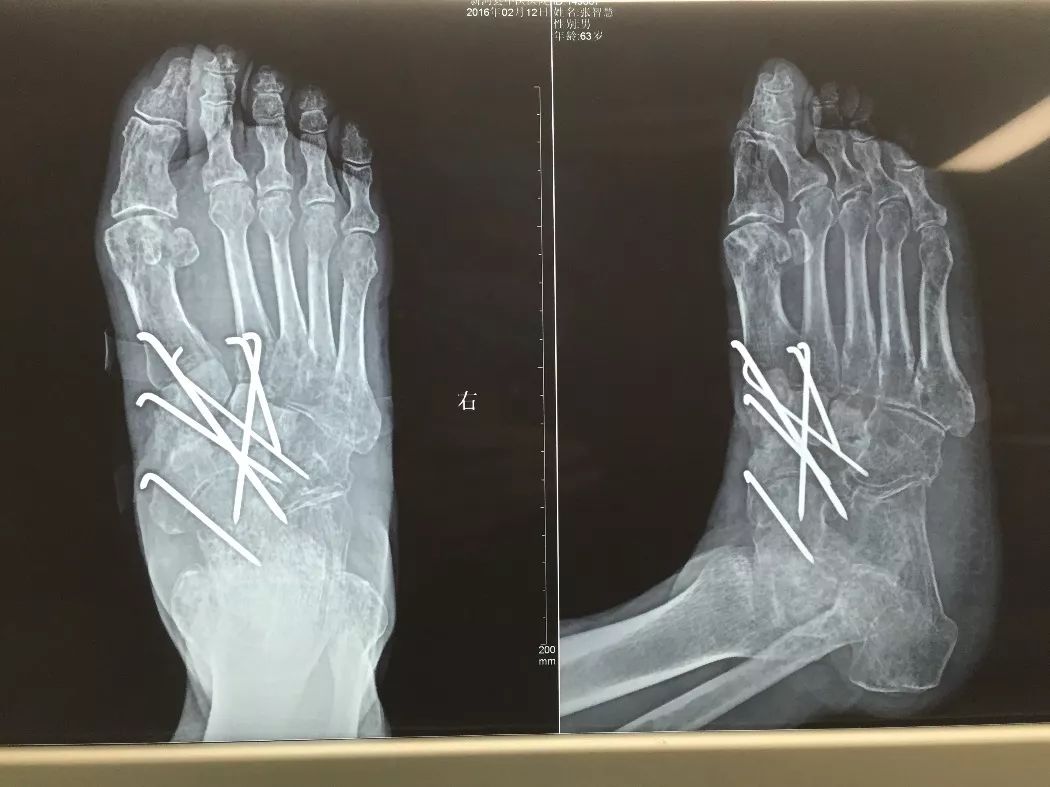

下面1例是我的学生所发。病史清楚,跗骨骨折后伤口开放,每次换药用双氧水冲洗伤口,造成骨坏死

跗骨感染

该例患者需要汲取的经验和教训:不要使用双氧水冲洗伤口死骨密度高是因为不参与代谢周围骨疏松治疗清理死骨后用骨水泥诱发诱导模反复几次做半开放植骨手术后走路刺激骨愈合,改善骨质愈合。